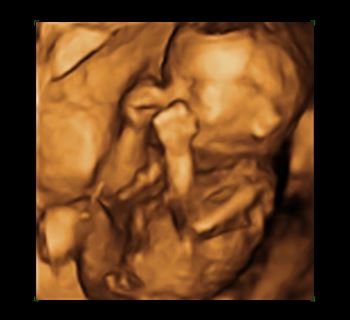

Raelyn was surprised…

… when she saw her baby. The ultra sound image revealed a VERY active little baby. She had no idea the baby would be moving so much at such an early stage of development.

Raelyn was seriously considering an abortion when she came to the Pregnancy Help Center. This changed everything. She cried as she watched the images on the screen.

Her relationship with the baby’s father was pretty new. Neither of them were ready for a “permanent” commitment. He wasn’t happy about the pregnancy, and was lobbying heavily for abortion. Raelyn was inclined to agree with him. Her life would certainly be much less complicated without a baby. That was, however, before she SAW her baby.

Now, everything had changed. Raelyn knew she could never end the life of this precious little baby.